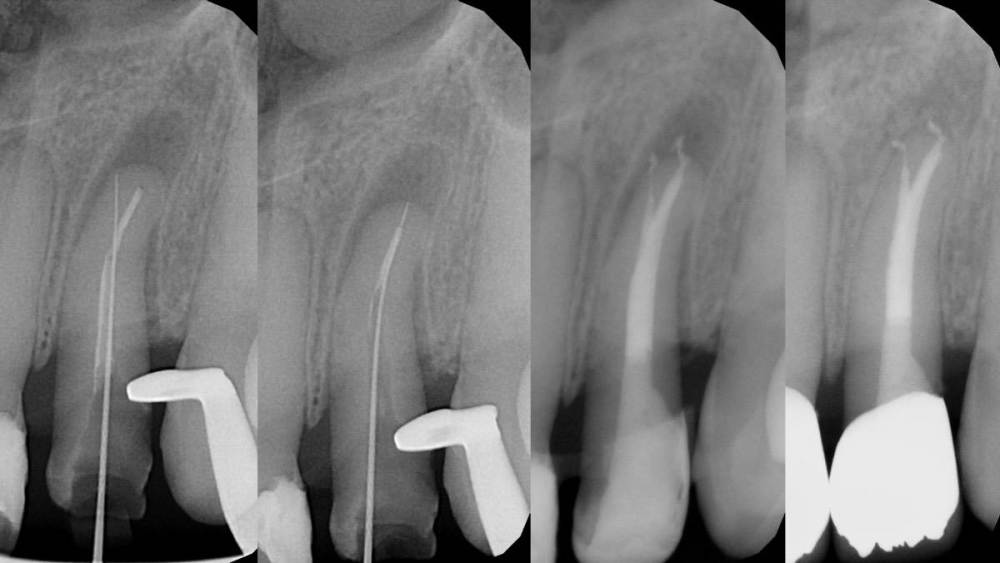

Гарриевич Опубликовано 21 марта, 2023 Автор Поделиться Опубликовано 21 марта, 2023 Пациент обратился с запросом обойти ступеньку и ложный ход в корневом канале образовавшиеся в ходе попытки перелечивания 2.2 зуба. Такде обнаружена глубокая поддесневая перфорация дистальной стенки закрытая композитом с признаками нарушения герметичности. Было решено произвести экструзию зуба 2.2 с последующим восстановлением коронкой. Экструзия производилась с помощью поперечно зафиксированного стекловолоконного штифта и ортодонтической цепочки. Из-за выраженной кривизны корня потребовалось 10 дней для достаточного вытяжения зуба. После вытяжения произведено эндодонтическое перелечивание и композитная надстройка культи. Зуб 2.2 зашинирован на 3 месяца. После периода ретенции ортопедом (Олег Саркисов) изготовлена провизорная коронка для формирования правильного десневого контура, которая через 3 недели была заменена на временную коронку длительного ношения. Через 4 месяца постоянная коронка из диоксида циркония зафиксирована на 2.2 зуб (также на 1.2/1.1/2.1). Осмотр через 1 год показывает хороший результат и сформировавшиеся десневые сосочки. Небольшой рубец пациента не беспокоит. Ортопед Олег Саркисов (bratok) Терапевт Юрий Кочаров 4 1 1 Ссылка на комментарий